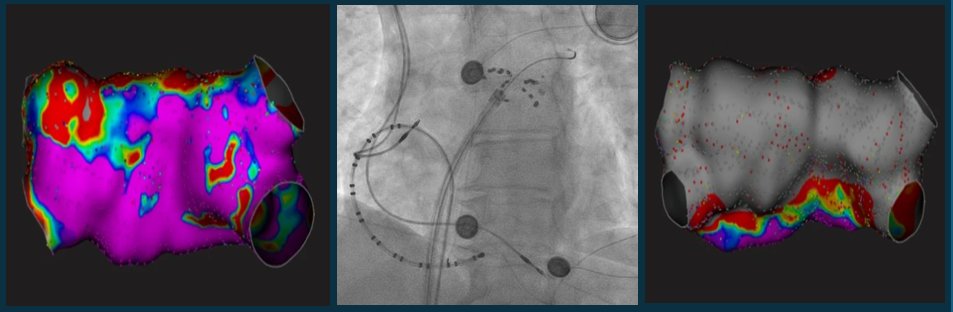

Kudos to our fellows & EP team @utmbcardiology on this first report of its kind in supporting the feasibility & safety of performing Farapulse PFA in patients who underwent LAAO w Watchman @deansabayon @carunnarayanan @HaiderTaii @utmbhealth #ACC #EP